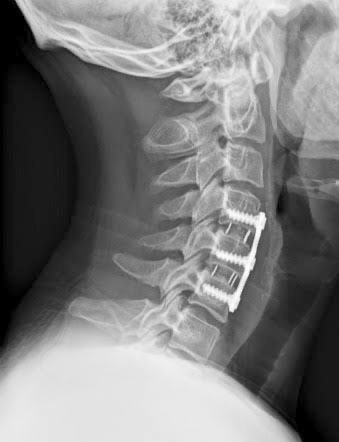

Cervical Decompression & Fusion Surgery